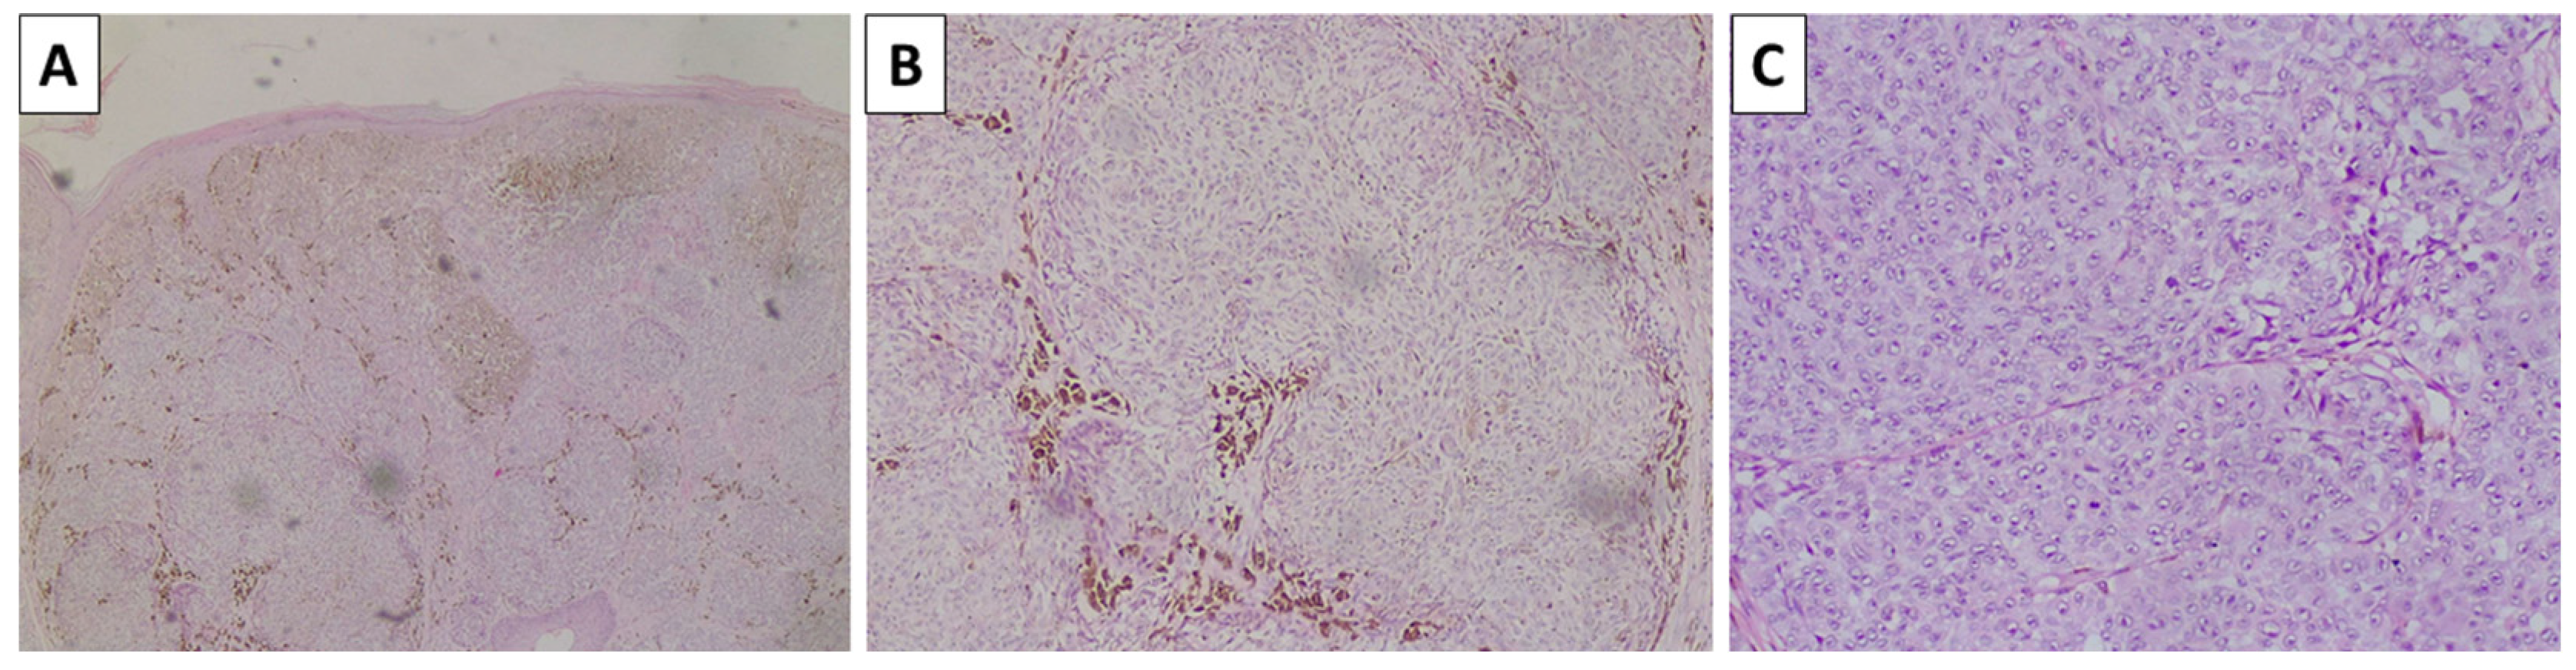

2.4. Case 5—Melanoma Arising in Blue Nevus